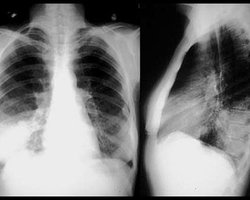

Украина Украинцы умирают не от пневмонии, а от дистресс-синдрома, - черновицкие судмедэксперты 13.11.2009 12:22